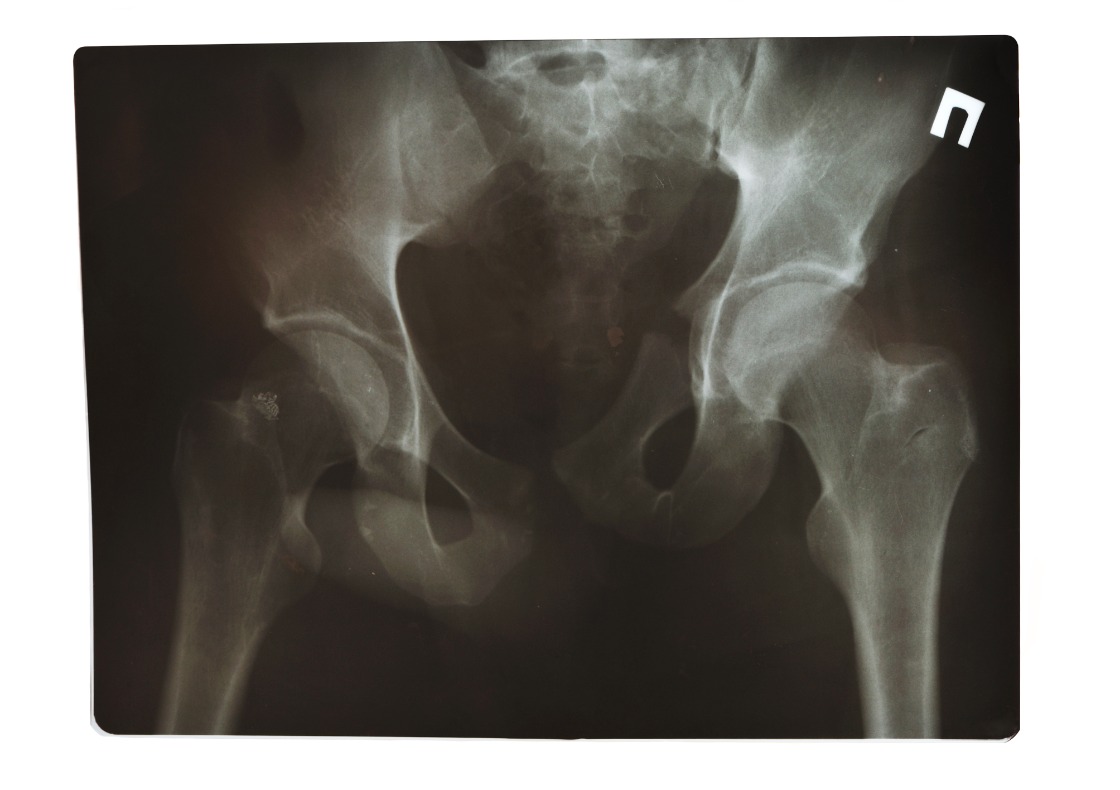

Het Anna Ziekenhuis in Geldrop heeft een wereldwijde primeur te pakken. De zorginstelling heeft als eerste ooit een 3D-geprinte heupimplantaat bij een mens geplaatst. Heupspecialist en orthopedisch chirurg Rintje Agricola voerde de operatie uit en deed dit samen met het Leids Universitair Medisch Centrum (LUMC). Dit meldt het LUMC.

De nieuwe behandeling is nog geen standaard onderdeel in de zorg, maar kan op termijn voorkomen dat patiënten met heupdysplasie een zware operatie moeten ondergaan. Deze patiënten hebben een afwijkend gevormde heupkom, waardoor de kop van de heup niet goed wordt ondersteund in het gewricht. Zij hebben vaak last van pijn, instabiliteit en mobiliteitsproblemen. Worden zij niet behandeld, kunnen vroegtijdige slijtage ontstaan en op vroege leeftijd een kunstheup nodig zijn. Momenteel moeten zij een heftige operatie ondergaan, waarbij chirurgen het bekken losmaken en opnieuw een plek geven. Patiënten moeten lang herstellen en kunnen dan maar weinig.